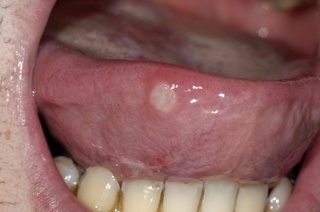

A mouth ulcer, otherwise known as a canker sore or an aphthous ulcer, occurs when there is a break in the skin of the mouth (mucosal lining), exposing the underlying connective tissue. It may have a 'crater-like' appearance and is often red and painful, similar to a blister in the mouth.

Unlike the relatively benign examples mentioned above, oral cancers may initially show up as a mouth ulcer. Oral cancer can present itself in many ways: some people first become aware of an ulcer that won't heal: these lesions are usually a painless mouth ulcer, but it doesn't come and go the way other mouth ulcers do. Any mouth ulcer that has been present for more than three weeks must be treated as serious until proven otherwise. Similarly, if you have developed a red , white or mixed red and white patch, you must urgently seek a professional opinion.